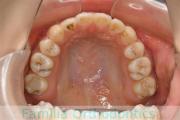

No.22V-299

- 上顎前突

- 叢生

- 30歳

- 女性

上の出っ歯、口が閉じにくい、下の前歯のガタガタを治したいということで来院されました。上顎から左右小臼歯を、下の前歯は凹凸が非常に強いので、こちらから一本抜歯を行いました。2年強、30回程度の通院が必要でした。

成人になってからの叢生(でこぼこ、凹凸、ガタガタ)は、保定をしっかりしないと後戻りをしてしまうリスクが高いです。